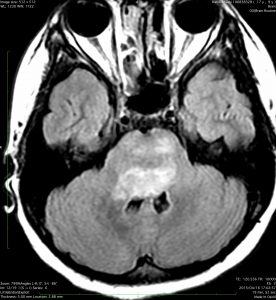

この脳幹部グリオーマは橋から小脳脚に浸潤したものです。びまん性橋膠腫の進行例にもみえますが,ガドリニウム増強のされ方が中心部で強すぎて非定型的です。これを生検術して病理確定診断をすれば,胎児性腫瘍やAP/RTという診断がつくのかもしれません。しかし,できることは局所放射線治療が主体の治療でなんらかの化学療法を組み合わせるくらいです。リスクの大きい病理診断で時を失うより早く治療を開始したほうがよいと思われる経過と画像でした。